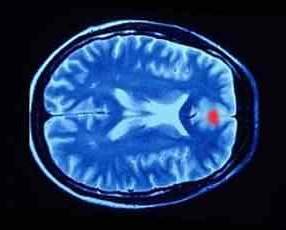

وبعد إجراء التجارب والتقاط العديد من الصور لجميع أجزاء الدماغ وجد العلماء أن الإنسان عندما يكذب فإن هنالك نشاطاً كبيراً تظهره الصور المغنطيسية بطريقة تسمى functional magnetic resonance imaging في منطقة محددة من الدماغ وهي منطقة أعلى ومقدمة هذا الدماغ [1].

وهكذا استنتج العلماء أن الجزء الأمامي العلوي من الدماغ هو المسؤول عن الكذب! وهذا الجزء هو ما نسميه في اللغة العربية بناصية الإنسان، أي أعلى ومقدمة الرأس، وهنا يتوضع هذا الجزء من الدماغ.

أظهرت الصور الحديثة للدماغ أثناء تجربة الكذب، أن المنطقة في أعلى ومقدمة الدماغ تنشط بشكل كبير أثناء الكذب، لاحظ البقعة الحمراء التي تشير إلى نشاط في مقدمة وأعلى الدماغ حين يكذب الإنسان.

ويقول العالم Scott Faro الذي أجرى هذه التجارب: عندما يقول الإنسان الحقيقة أي عندما يكون صادقاً، تكون المنطقة ذاتها في الدماغ أي الجزء الأمامي في حالة نشاط أيضاً، ويمكن أن نستنتج أن منطقة الناصية هي المسؤولة عن الصدق أو الكذب.